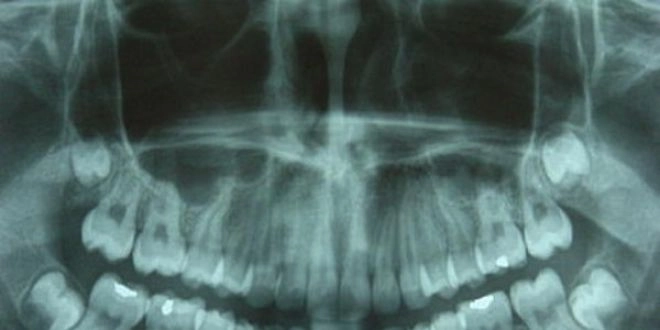

Quoi qu'il en soit, les doses reçues sont infinitésimales, et le sont d'autant plus depuis que le matériel a évolué. "Depuis plusieurs années, les dentistes utilisent des capteurs numériques, très sensibles, qui ont permis de faire encore baisser les quantités de rayonnements à utiliser par rapport à l'argentique." Pour se faire une idée, une radiographie panoramique (qui couvre l'ensemble de la mâchoire) expose à une dose de rayonnement comparable à celle reçue lors d'un vol Paris- New York en avion… "Dans les cabinets dentaires, les doses administrées n'ont rien à voir avec celle reçues, par exemple, lors d'une radio abdominale", précise le chirurgien dentiste.